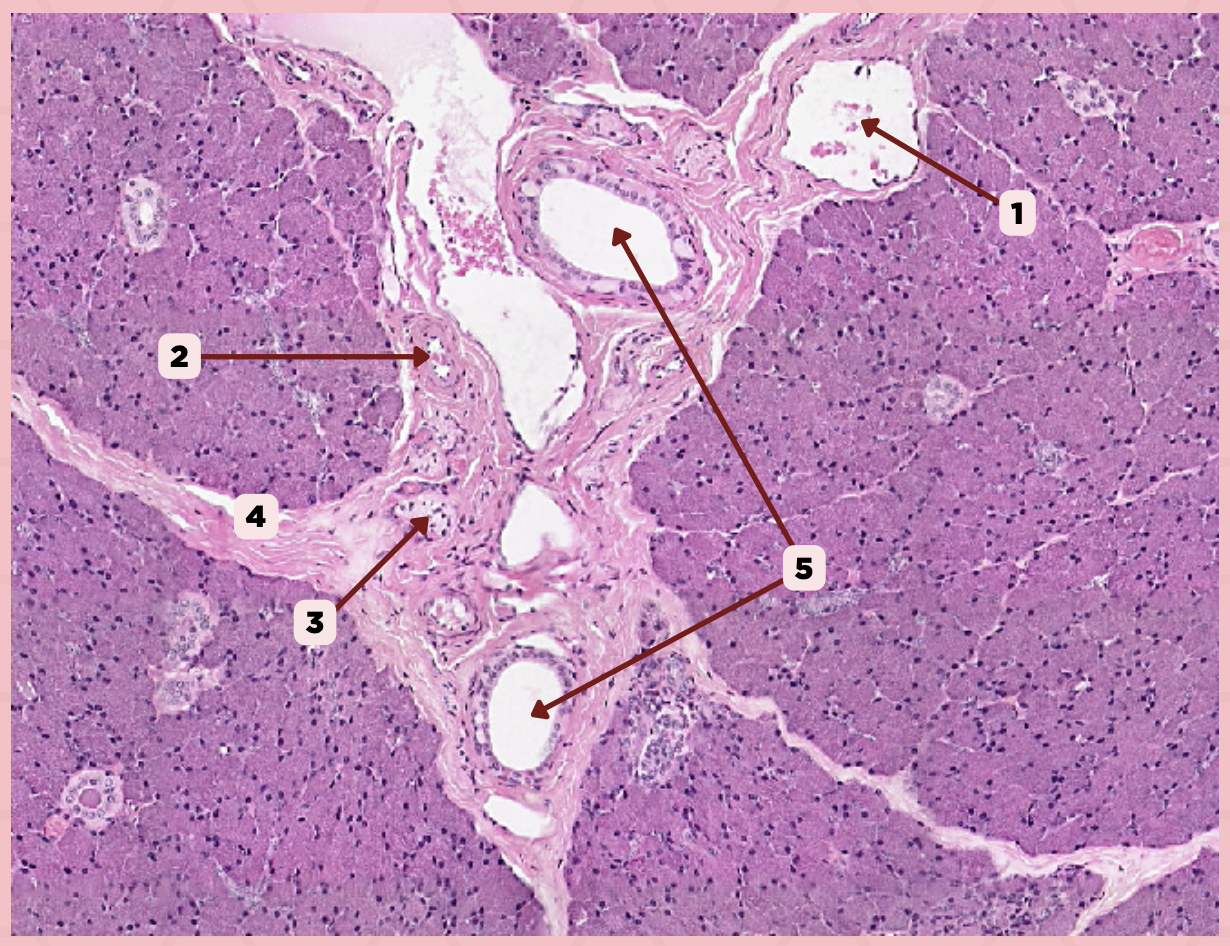

Parotid

Vein

Identify the structure labeled as 1.

Artery

Identify the structure labeled as 2.

Nerve

Identify the structure labeled as 3.

Interlobular Septa

Identify the structure labeled as 4.

Interlobular Duct

Identify the structure labeled as 5.